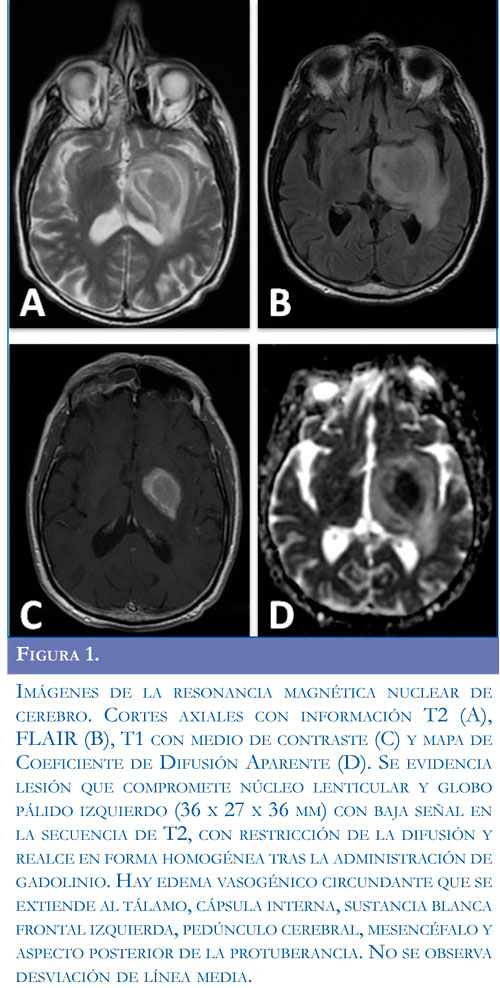

medio de contraste y espectroscopia que evidenció una lesión única en los núcleos grises izquierdos de la base, altamente sugestiva de una neoplasia de tipo linfoide (Figuras 1 y 2). Se planteó el diagnóstico de un linfoma primario del sistema nervioso central post-trasplante (PTLD-PSNC), por lo que se suspendió el MMF, continuando la ciclosporina a la misma dosis. Se practicó una punción lumbar con estudio citológico negativo y citoquímico que mostró únicamente proteínas aumentadas y linfocitos B policlonales por citometría de flujo.

Imágenes de la resonancia magnética nuclear de cerebro. Cortes axiales con información T2 (A), FLAIR (B), T1 con medio de contraste (C) y mapa de Coeficiente de Difusión Aparente (D). Se evidencia lesión que compromete núcleo lenticular y globo pálido izquierdo (36 x 27 x 36 mm) con baja señal en la secuencia de T2, con restricción de la difusión y realce en forma homogénea tras la administración de gadolinio. Hay edema vasogénico circundante que se extiende al tálamo, cápsula interna, sustancia blanca frontal izquierda, pedúnculo cerebral, mesencéfalo y aspecto posterior de la protuberancia. No se observa desviación de línea media.

En su mayoría, los hallazgos en la RM tienden a seguir los patrones de los LPSNC (21), encontrando lesiones multifocales intra-axiales, con predominio supratentorial (61% a 88%), con predilección hacia la zona periventricular y de los núcleos grises de la base (75%). Es infrecuente el compromiso leptomeníngeo o de la médula espinal. Las imágenes obtenidas en las secuencias T2 tienden a mostrar lesiones hipoin-tensas con aumento en la señal perilesional correspondiente a edema vasogénico, mientras que en las secuencias T1 precontraste, las lesiones se muestran hipointensas en comparación con la corteza normal. Una vez contrastadas las lesiones presentan patrones variables que comprenden el realce heterogéneo en la mayoría (56%), homogéneo (41%) y anular (29%) (20,22). El uso de la espectroscopia por resonancia magnética de protones otorga algunas claves sobre la información metabólica in vivo. En el LPSNC, al igual que en otros tumores del SNC se observa un aumento marcado de la colina (Cho), con una disminución de los picos de N-acetil-aspartato (NAA). La presencia de picos de lípidos sobre las zonas no necróticas de la lesión expansiva es el signo más específico y sugestivo de LPSNC (23). Este caso se presentó con una lesión única que comprometía los núcleos grises de la base, hipointensa en T2, con realce homogéneo con el medio de contraste y un patrón característico por espectroscopia, lo que permitió sospechar como primera posibilidad el diagnóstico de un PLTD.